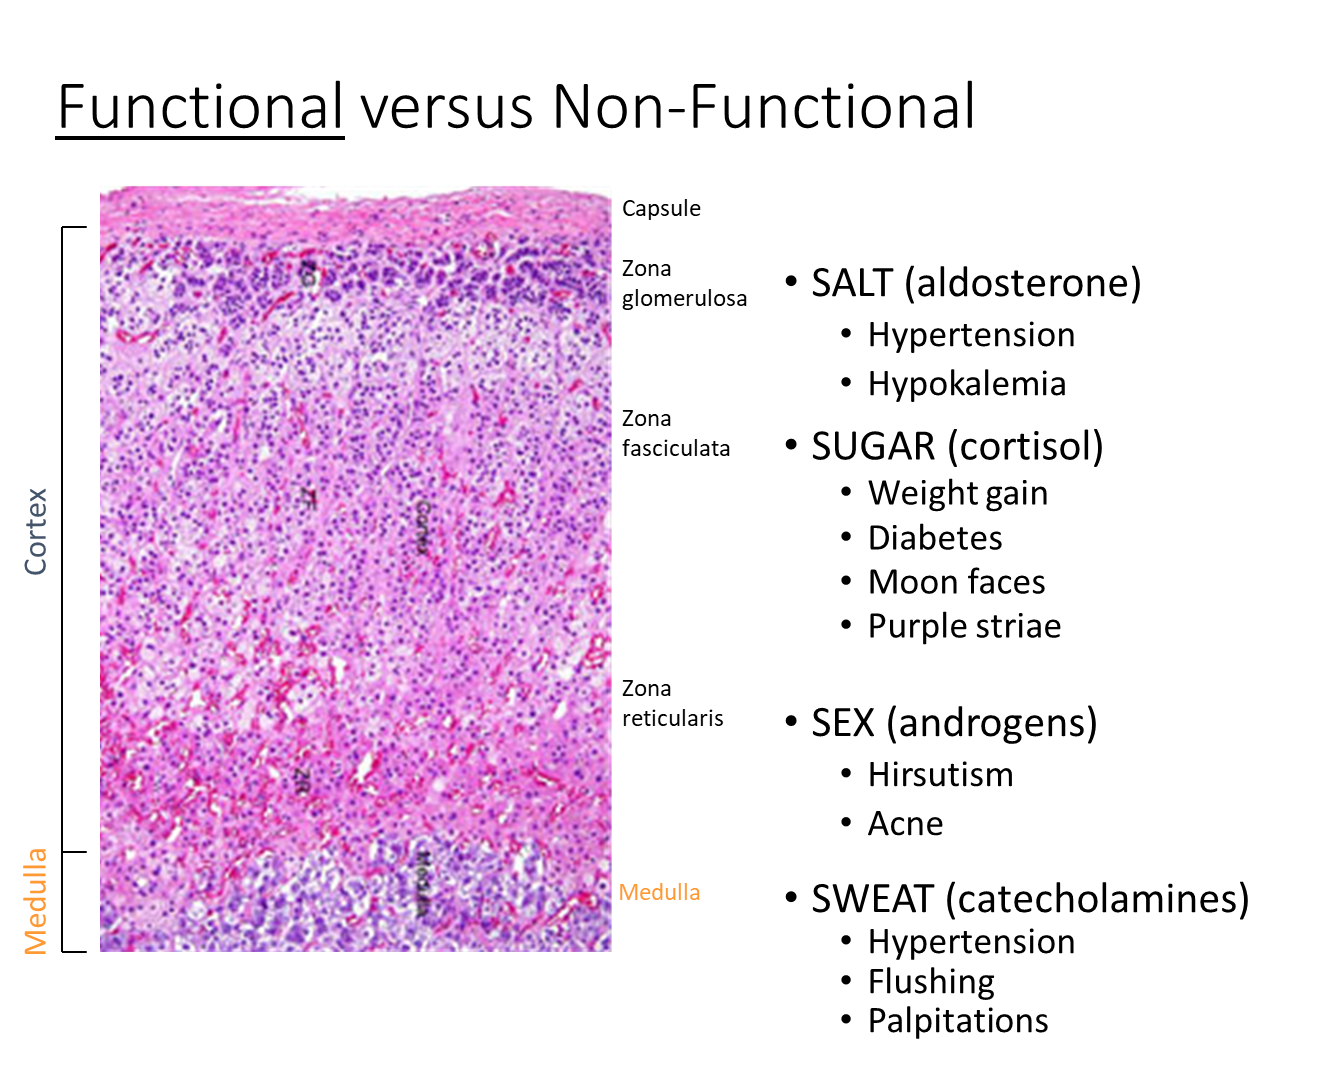

What are the symptoms of functional tumors found at each adrenal layer?

1) Zona Glomerulosa - SALT/Aldosterone

→ Hypertension

→ Hypokalemia

2) Zona Fasciculata - SUGAR/Cortisol

→ Weight Gain

→ Diabetes

→ Moon Faces

→ Purple Striae

3) Zona Reticualris - SEX/Androgens

→ Hirsutism (excessive hair growth)

→ Acne

4) Medulla - SWEAT/Catecholamines

→ Flushing

→ Palpitations